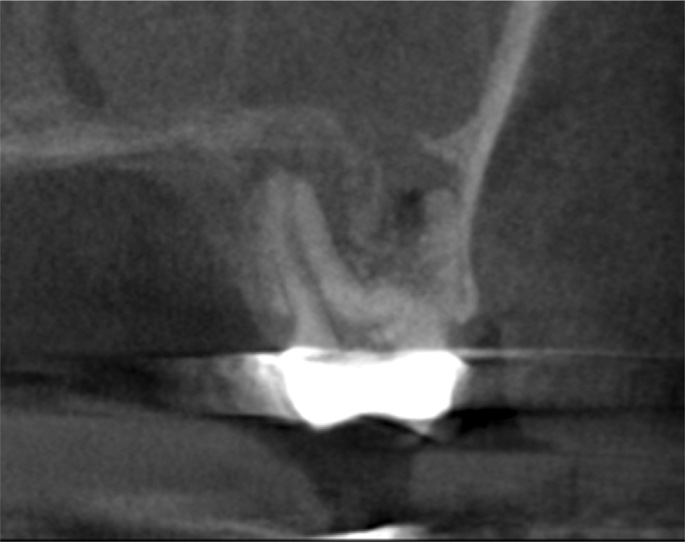

(3.) Sagittal slice of CBCT image of the same tooth displaying PAO or “halo lesion” with associated mucositis.

Figure 3

(4.) Coronal slice of CBCT image of the same tooth.

Figure 4

For patients suffering from MSEO, radiographs will reveal a periapical radiolucency with adjacent opacification in the maxillary sinus.12 Additional radiographic findings associated with MSEO include periapical mucositis and periapical osteoperiostitis (PAO). Periapical mucositis refers to mucosal thickening or dome-shaped soft-tissue expansion on the floor of the sinus directly adjacent to the infected root apex.PAO refers to the reactive osteogenesis caused by a local periosteal reaction that expands the sinus periosteum and displaces it upward into the sinus. It appears as a radiopaque "halo" surrounding the root apex (Figure 2 through Figure 4). PAO may be symptomatic and/or accompanied by adjacent mucosal edema and elevated sinus fluid levels.9 If left untreated, PAO can progress and result in a direct communication between the root apex and maxillary sinus.6,13 Unless bilateral odontogenic pathosis is found, the sinus opacifications will usually be unilateral and centered around the odontogenic source. Complete unilateral sinus opacifications may be missed on the CBCT images typically used in endodontics due to their limited or focused field of view (Figure 5). In cases involving complete unilateral sinus opacification, referral to an ENT or oral surgeon is essential to rule out invasive fungal infection or malignancy.2,17,24